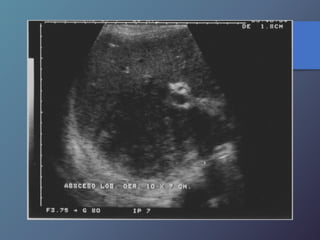

Abscesos Hepáticos Bacterianos

• Extensión directa por vía biliar-portal o

traumática.

• Características ecográficas variables

hipoecoicas.

• Artefactos de reverberación por

presencia de gas.

• Tabiques internos.

• Pared variable desde bien definida a

irregular y gruesa.

Abscesos Hepáticos Bacterianos •Extensión directa por vía biliar-portal o traumática. • Características ecográficas variables hipoecoicas. • Artefactos de reverberación por presencia de gas. • Tabiques internos. • Pared variable desde bien definida a irregular y gruesa.